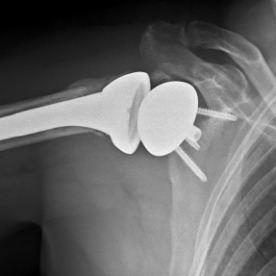

13) Impingementsyndrom der Schulter

Engpasssyndrom zwischen dem Schulterdach (Acromion) und den darunter liegenden Weichteilen (Rotatorenmanschette, Schleimbeutel). Die Schleimbeutelentzündung kann sich chronifizieren, teilweise entstehen reaktive Kalkablagerungen in den jeweiligen Sehnenansätzen. Die Therapie ist vorwiegend konservativ. Bei länger andauernder Beschwerdesymptomatik und ausgeschöpfter konservativer Therapie ist eine operative Therapie (in der Regel arthroskopisch) notwendig. Hierbei wird das entzündete Gewebe entfernt und die Unterkante des Acromion abgetragen. Somit wird eine Erweiterung dieses sog. subacromialen Raumes und damit eine Druckentlastung erreicht. Der Eingriff wird ambulant in unserer Praxis durchgeführt.